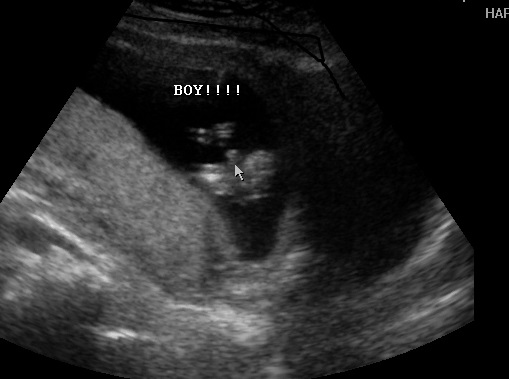

We just got back from our elective u/s, and the tech thinks we are having a boy. Our perinatologist told us he was almost certain it was a girl at our NT scan, as he did with DD, but he might have been wrong this time around. I'm still a little weary since the machine today wasn't as good as the one our doctor used a few weeks ago and since it's still so early. It'll be awesome when we get told girl at our A/S next month.

Either way, seeing baby was fun!